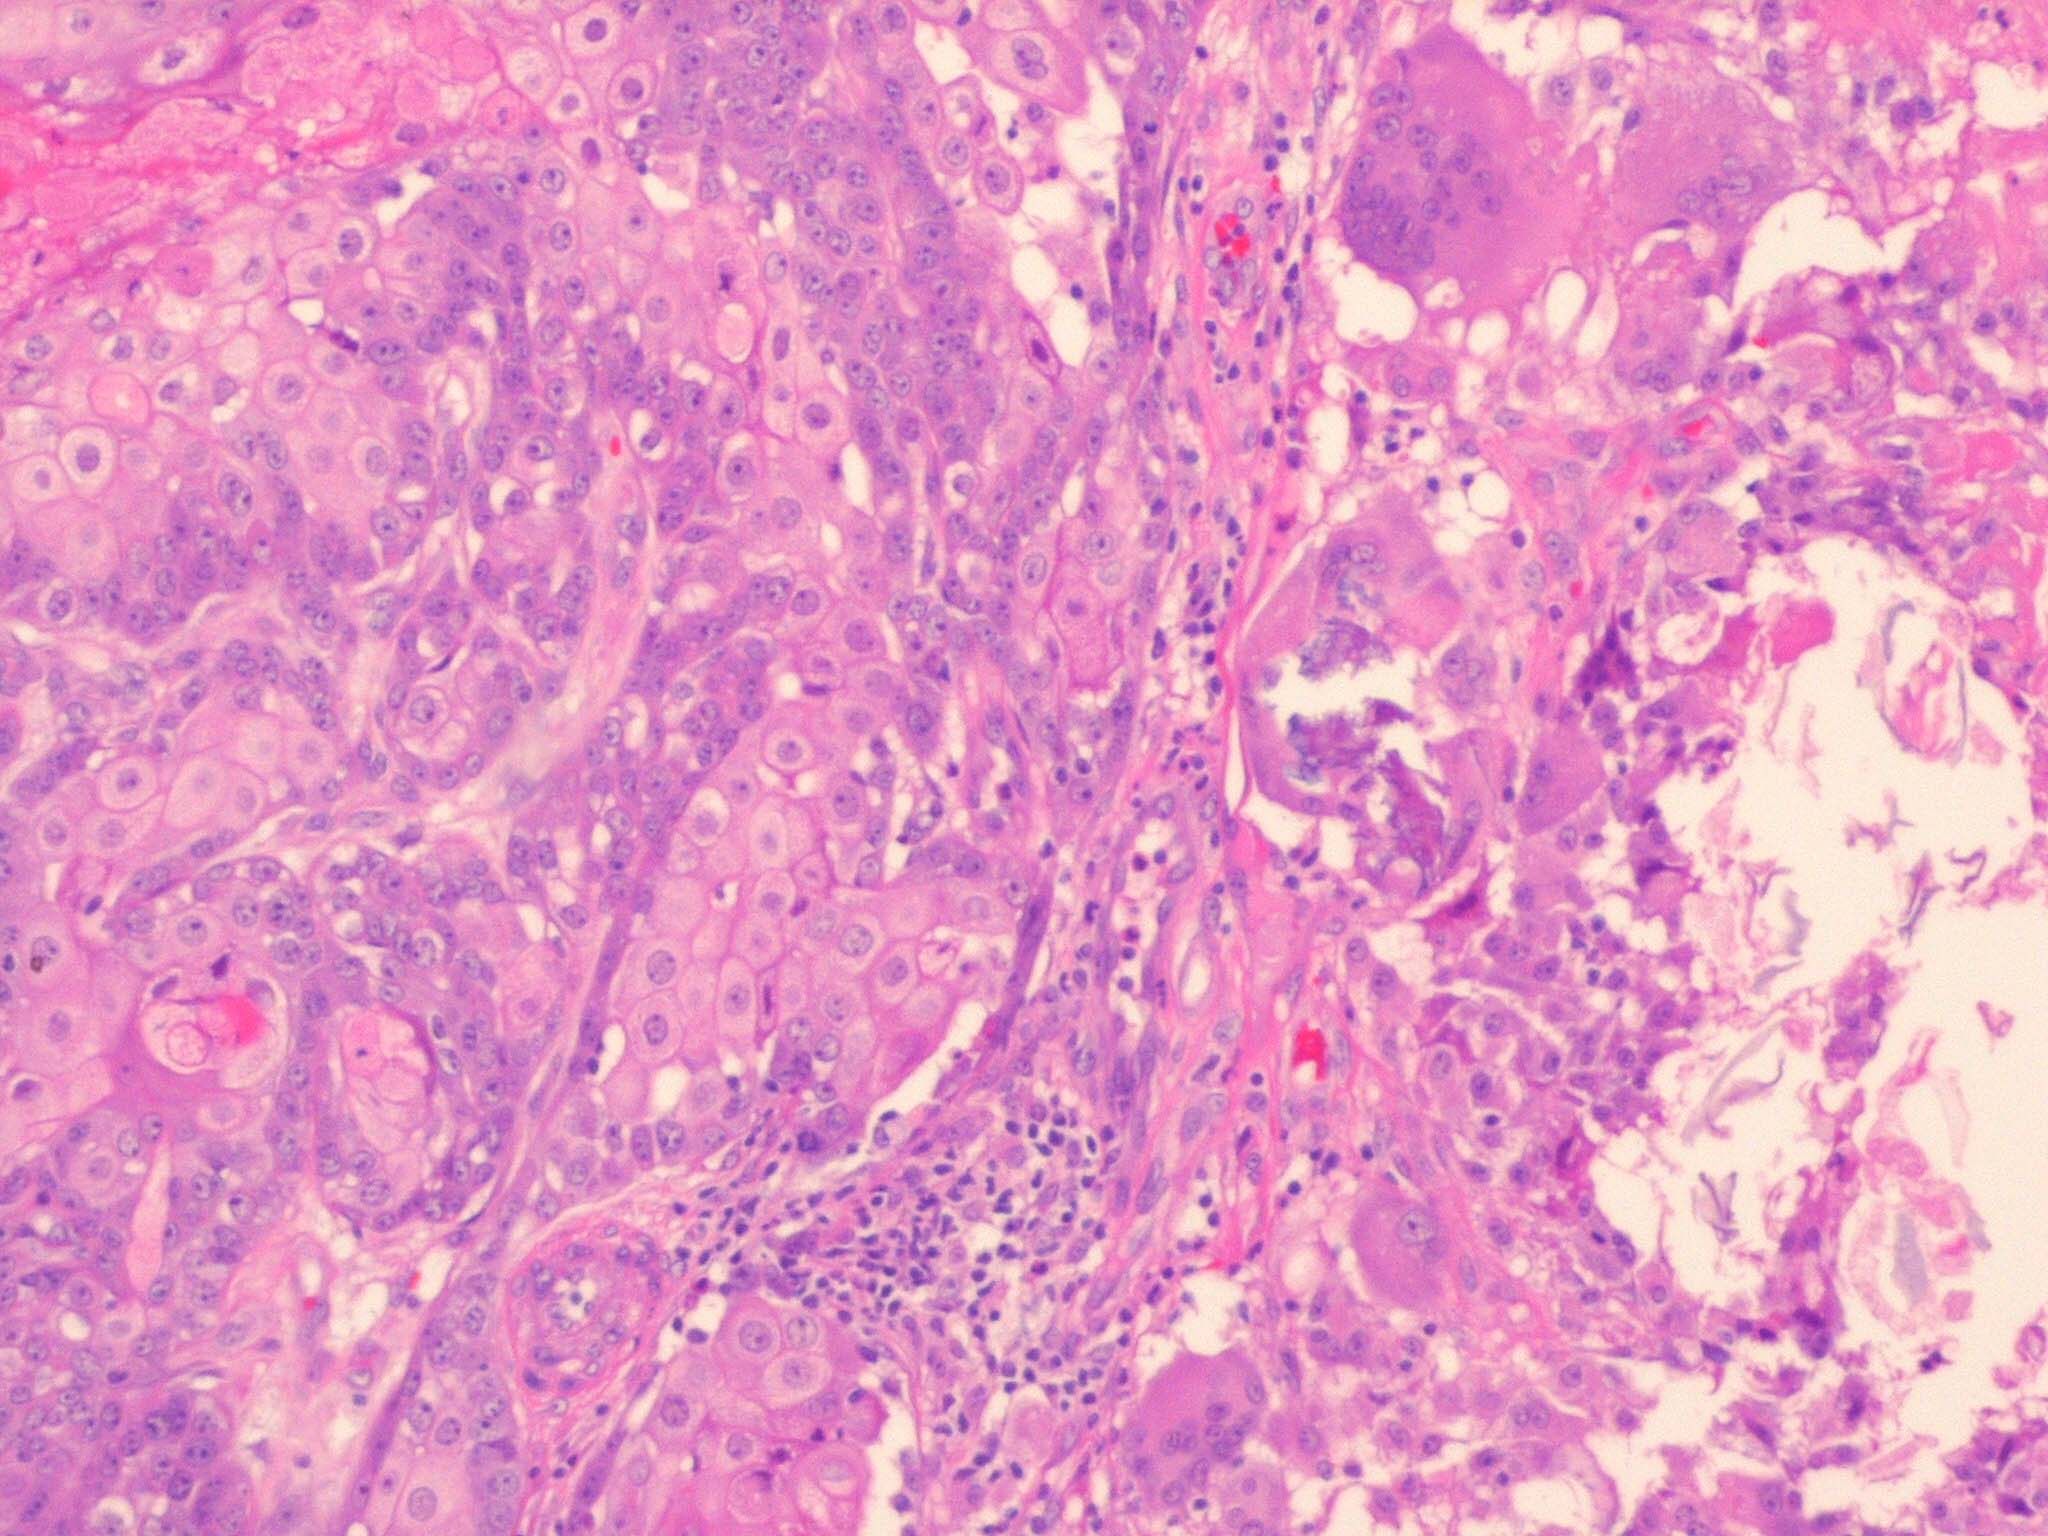

Sebaceous carcinoma = الكارسينوما الدهنية